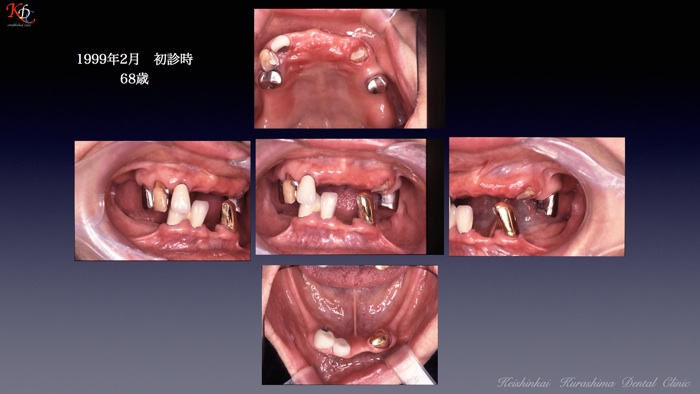

治 療例 1